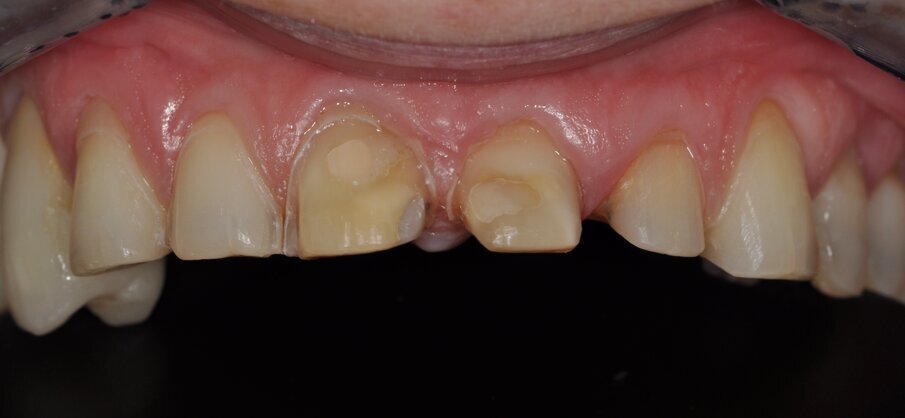

Fig. 5: Preparation of the partial crowns and the veneers, occlusal view

The preparations (Fig. 5) followed the preparation guidelines for all-ceramic restorations1 and the appropriate minimum wall thickness requirements for lithium silicate ceramic restorations. The preparation for the partial crowns 24 and 25 had rounded interior line angles and a 90° shoulder at the preparation margin. To prepare for the veneers (13, 12, 11, 23), approximately 0.5–0.7 mm of hard tissue was removed on the labial aspect and a 0.5 mm chamfer provided (Fig. 6). The intact proximal surfaces remained untouched. Otherwise, the teeth were prepared for circular full veneers (“360-degree veneers”). The crowns of teeth 21 and 22 were prepared with a 1-mm circular shoulder. Reduction of the incisal edges could be dispensed with as a consequence of raising the bite by 2 mm.